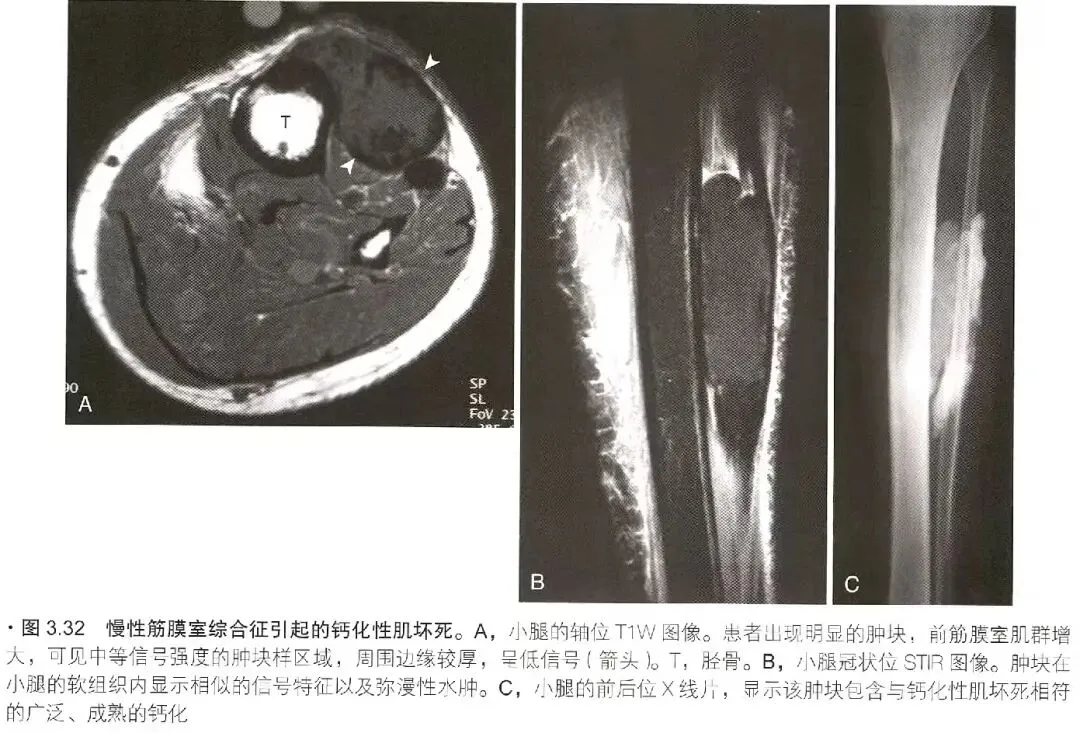

筋膜室综合征